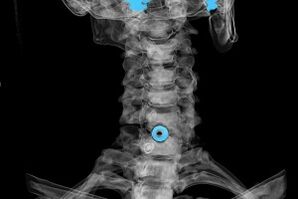

Diagnóza sa stanovuje na základe charakteristických symptómov, ako aj pomocou:

- röntgenové lúče. Metóda je neúčinná, najmä v posledných štádiách vývoja osteochondrózy.

- MRI (zobrazovanie magnetickou rezonanciou) krčnej chrbtice. Metóda, ktorá umožňuje vidieť kostné štruktúry, herniované medzistavcové platničky, ich veľkosť a smer vývoja.

- Počítačová tomografia. Menej účinné riešenie ako MRI, pretože je ťažké určiť prítomnosť a veľkosť hernií.